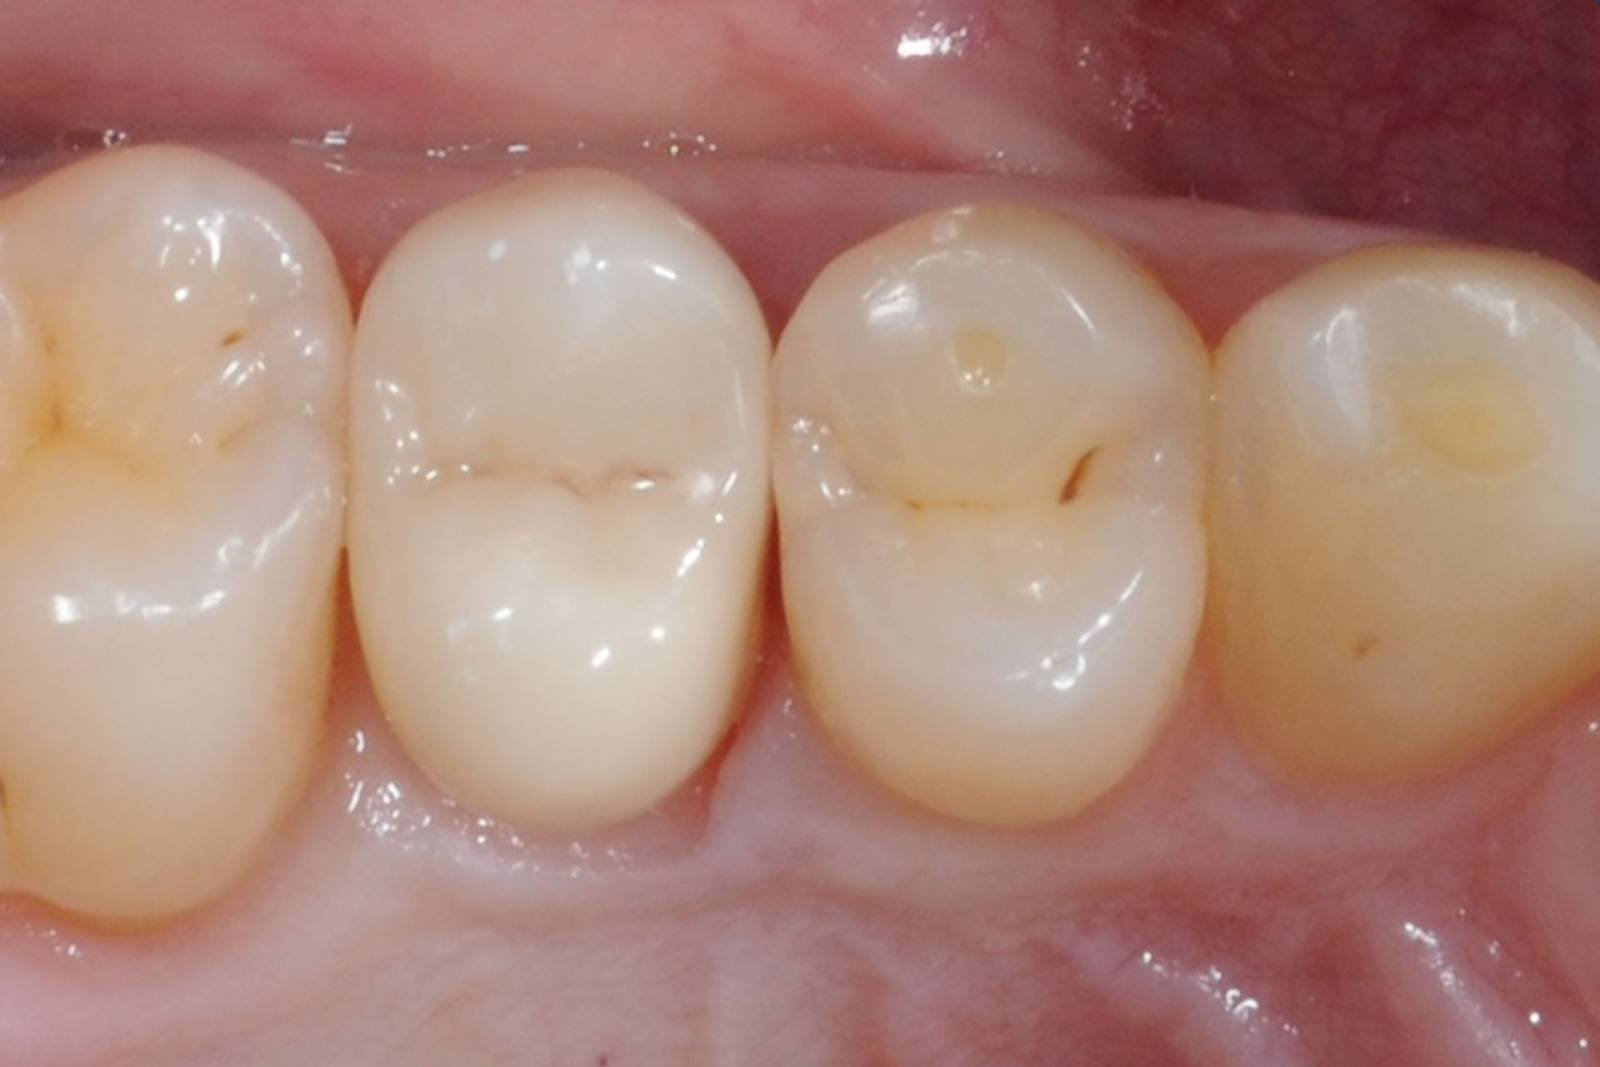

Quadrant rehabilitation

Two CEREC Tessera crowns and two inlays

Within a single visit of four hours the restoration of two crowns and two inlays, which were 15 years old, was carried out. The patient was very pleased with the very good esthetic result.

Before: Insufficient fillings in the second quadrant. The restorations were about 15 years old.

After: Chairside-fabricated crowns made from CEREC Tessera (teeth 26/27). Inlays for teeth 24 and 25 made of composite blocks.